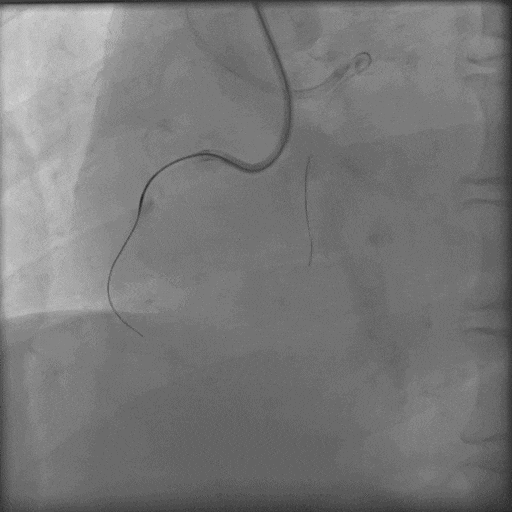

3.0后扩球囊Base;

导丝怎么扩秦川论剑|张勇:攻坚克难——解决器械难以通过的CTO病变之技术图谱_https://www.jmylbn.com_新闻资讯_第20张

P200短距离前行后再也不能前行,

导丝怎么扩秦川论剑|张勇:攻坚克难——解决器械难以通过的CTO病变之技术图谱_https://www.jmylbn.com_新闻资讯_第21张

Gaia3磨进2段,进入内膜下,前进艰难;